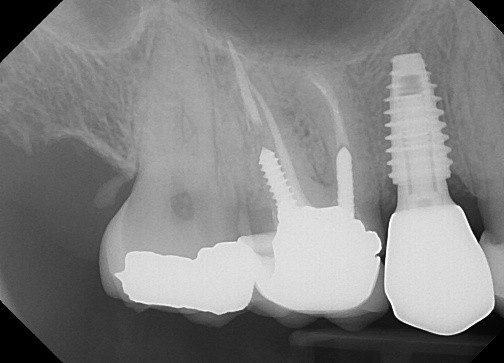

16. (Select ONE OR MORE correct answer)

There is radiographic evidence of

Regarding tooth 4.6, there is evidence of

Regarding dental implant at site 3.6, there is evidence of